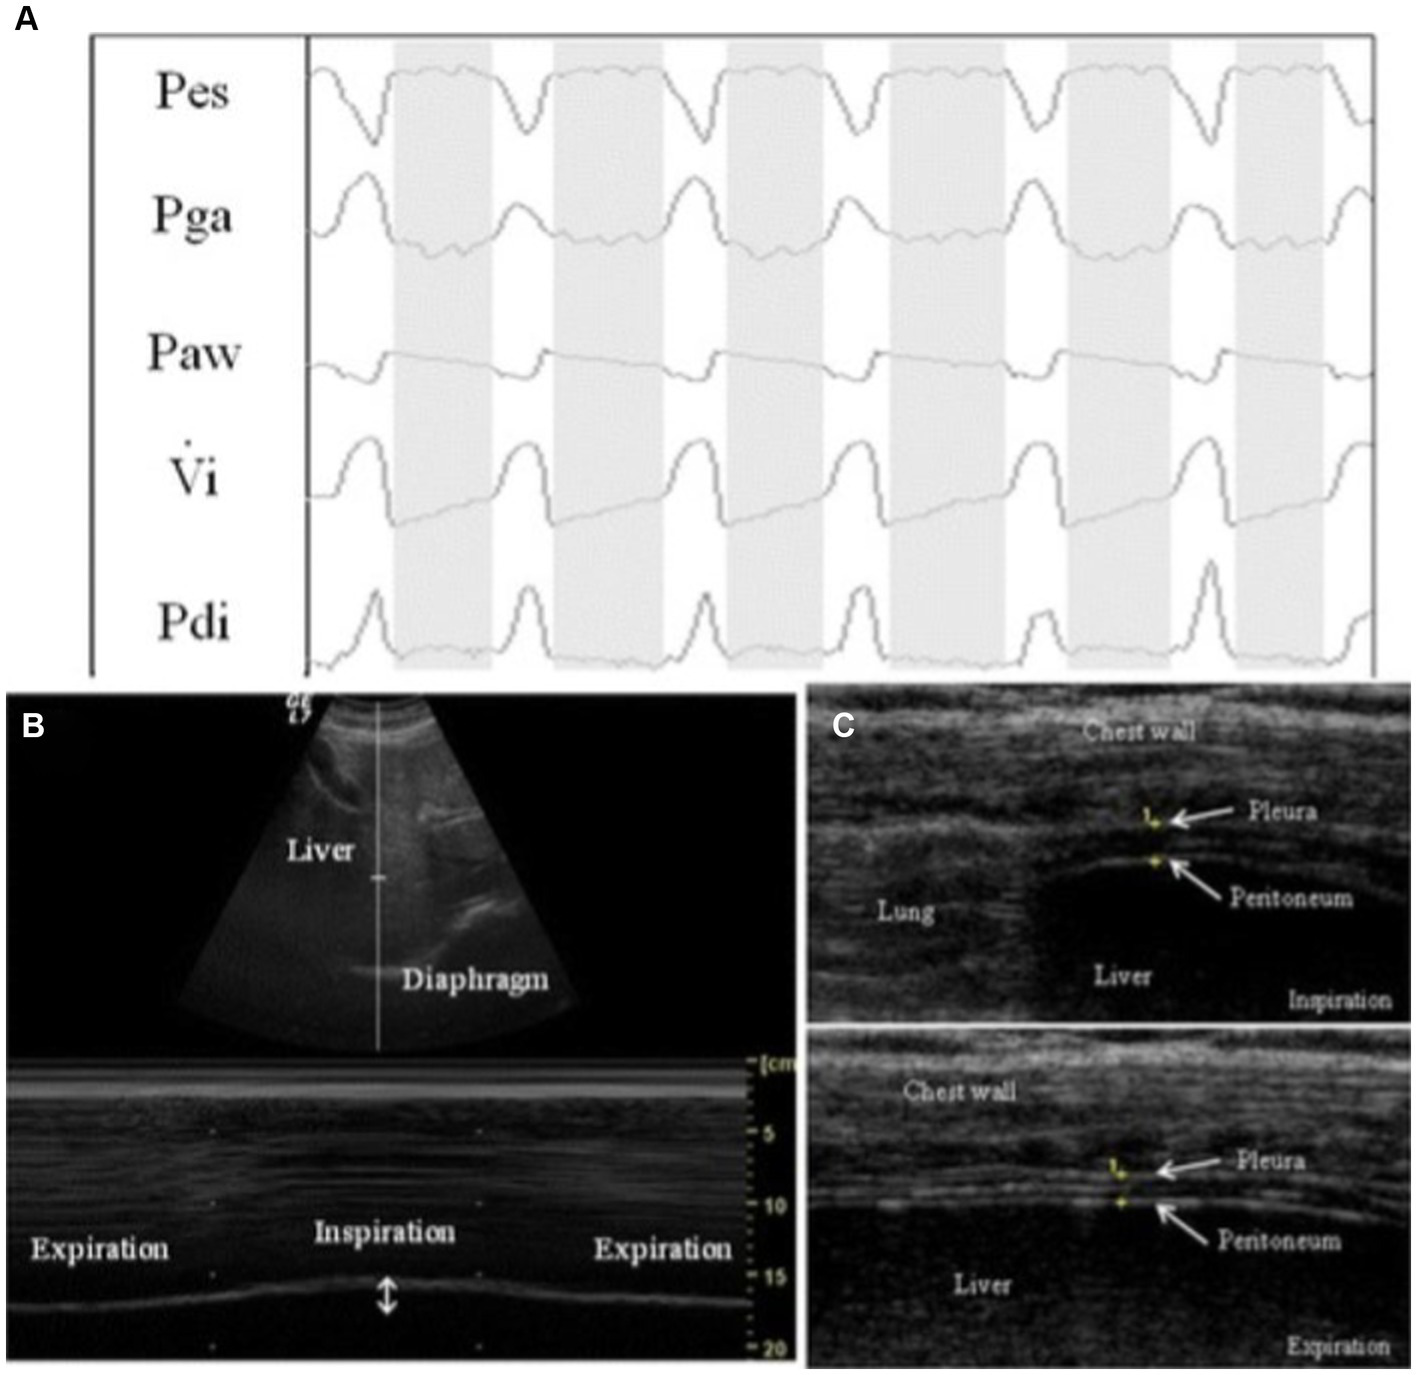

Figure 5

Example of respiratory tracings with ultrasound measurements during a pressure support of 0 cm H2O (PS0 step). (A) Respiratory tracings showing: Pes, esophageal pressure; Pga, gastric pressure; Paw, airway pressure; Vi, respiratory flow; Pdi, transdiaphragmatic pressure. The white columns represent inspiration and gray columns represent expiration phases. (B) Ultrasound view of diaphragm excursion during spontaneous breathing in B-mode (upper) and M-mode (lower). (C) Ultrasound view of the diaphragm in the zone of apposition during inspiration (upper) and during expiration (lower). The diaphragm is the three-layer structure in the middle consisting of a hypoechoic central layer sounded by an echogenic diaphragmatic pleurae and peritoneum, as indicated by the yellow arrows. This image was adopted with the permission of the Creative Commons license. No changes were made to this image. The Creative Commons Public Domain Dedication waiver (http://creativecommons.org/publicdomain/zero/1.0/) applies to this image (40).